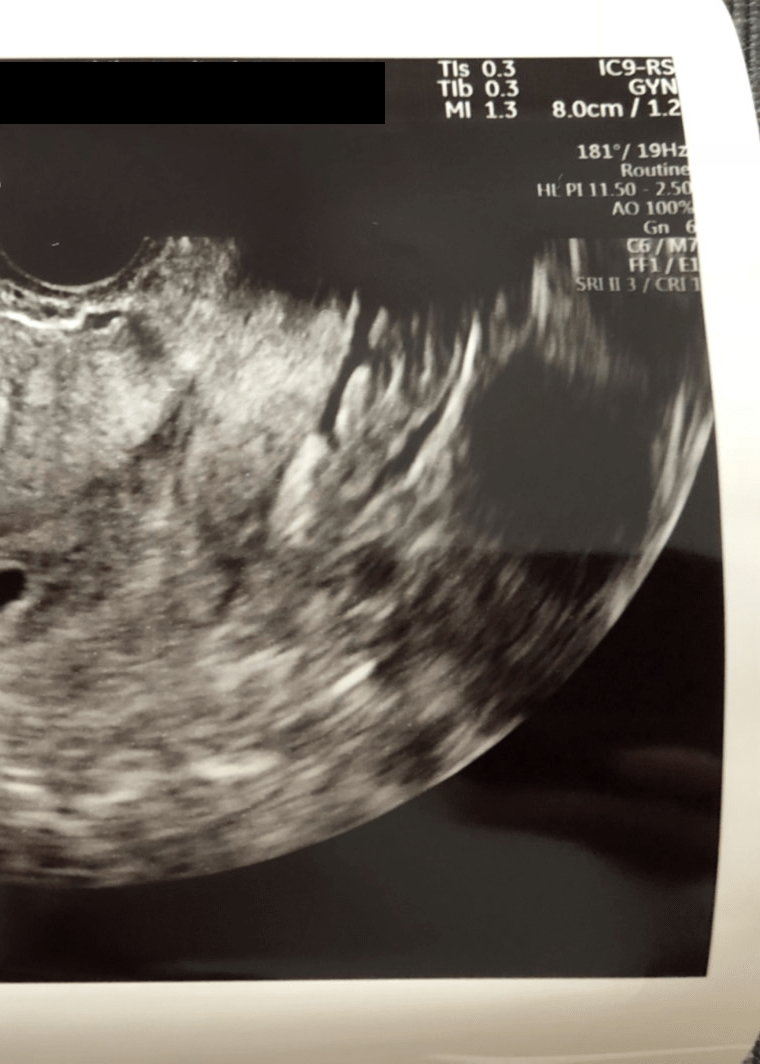

「双子かもしれない」――。医師からそう告げられた瞬間、モリさんの頭の中は「えーー!!!!????」という驚きでいっぱいになったと言います。

「『あれ?袋が2つあるな…(胎嚢のことだったと思います)様子を見ないとわかりませんが、双子の可能性があります』と。あの“袋2つ”というフレーズが、すごく印象に残っています」